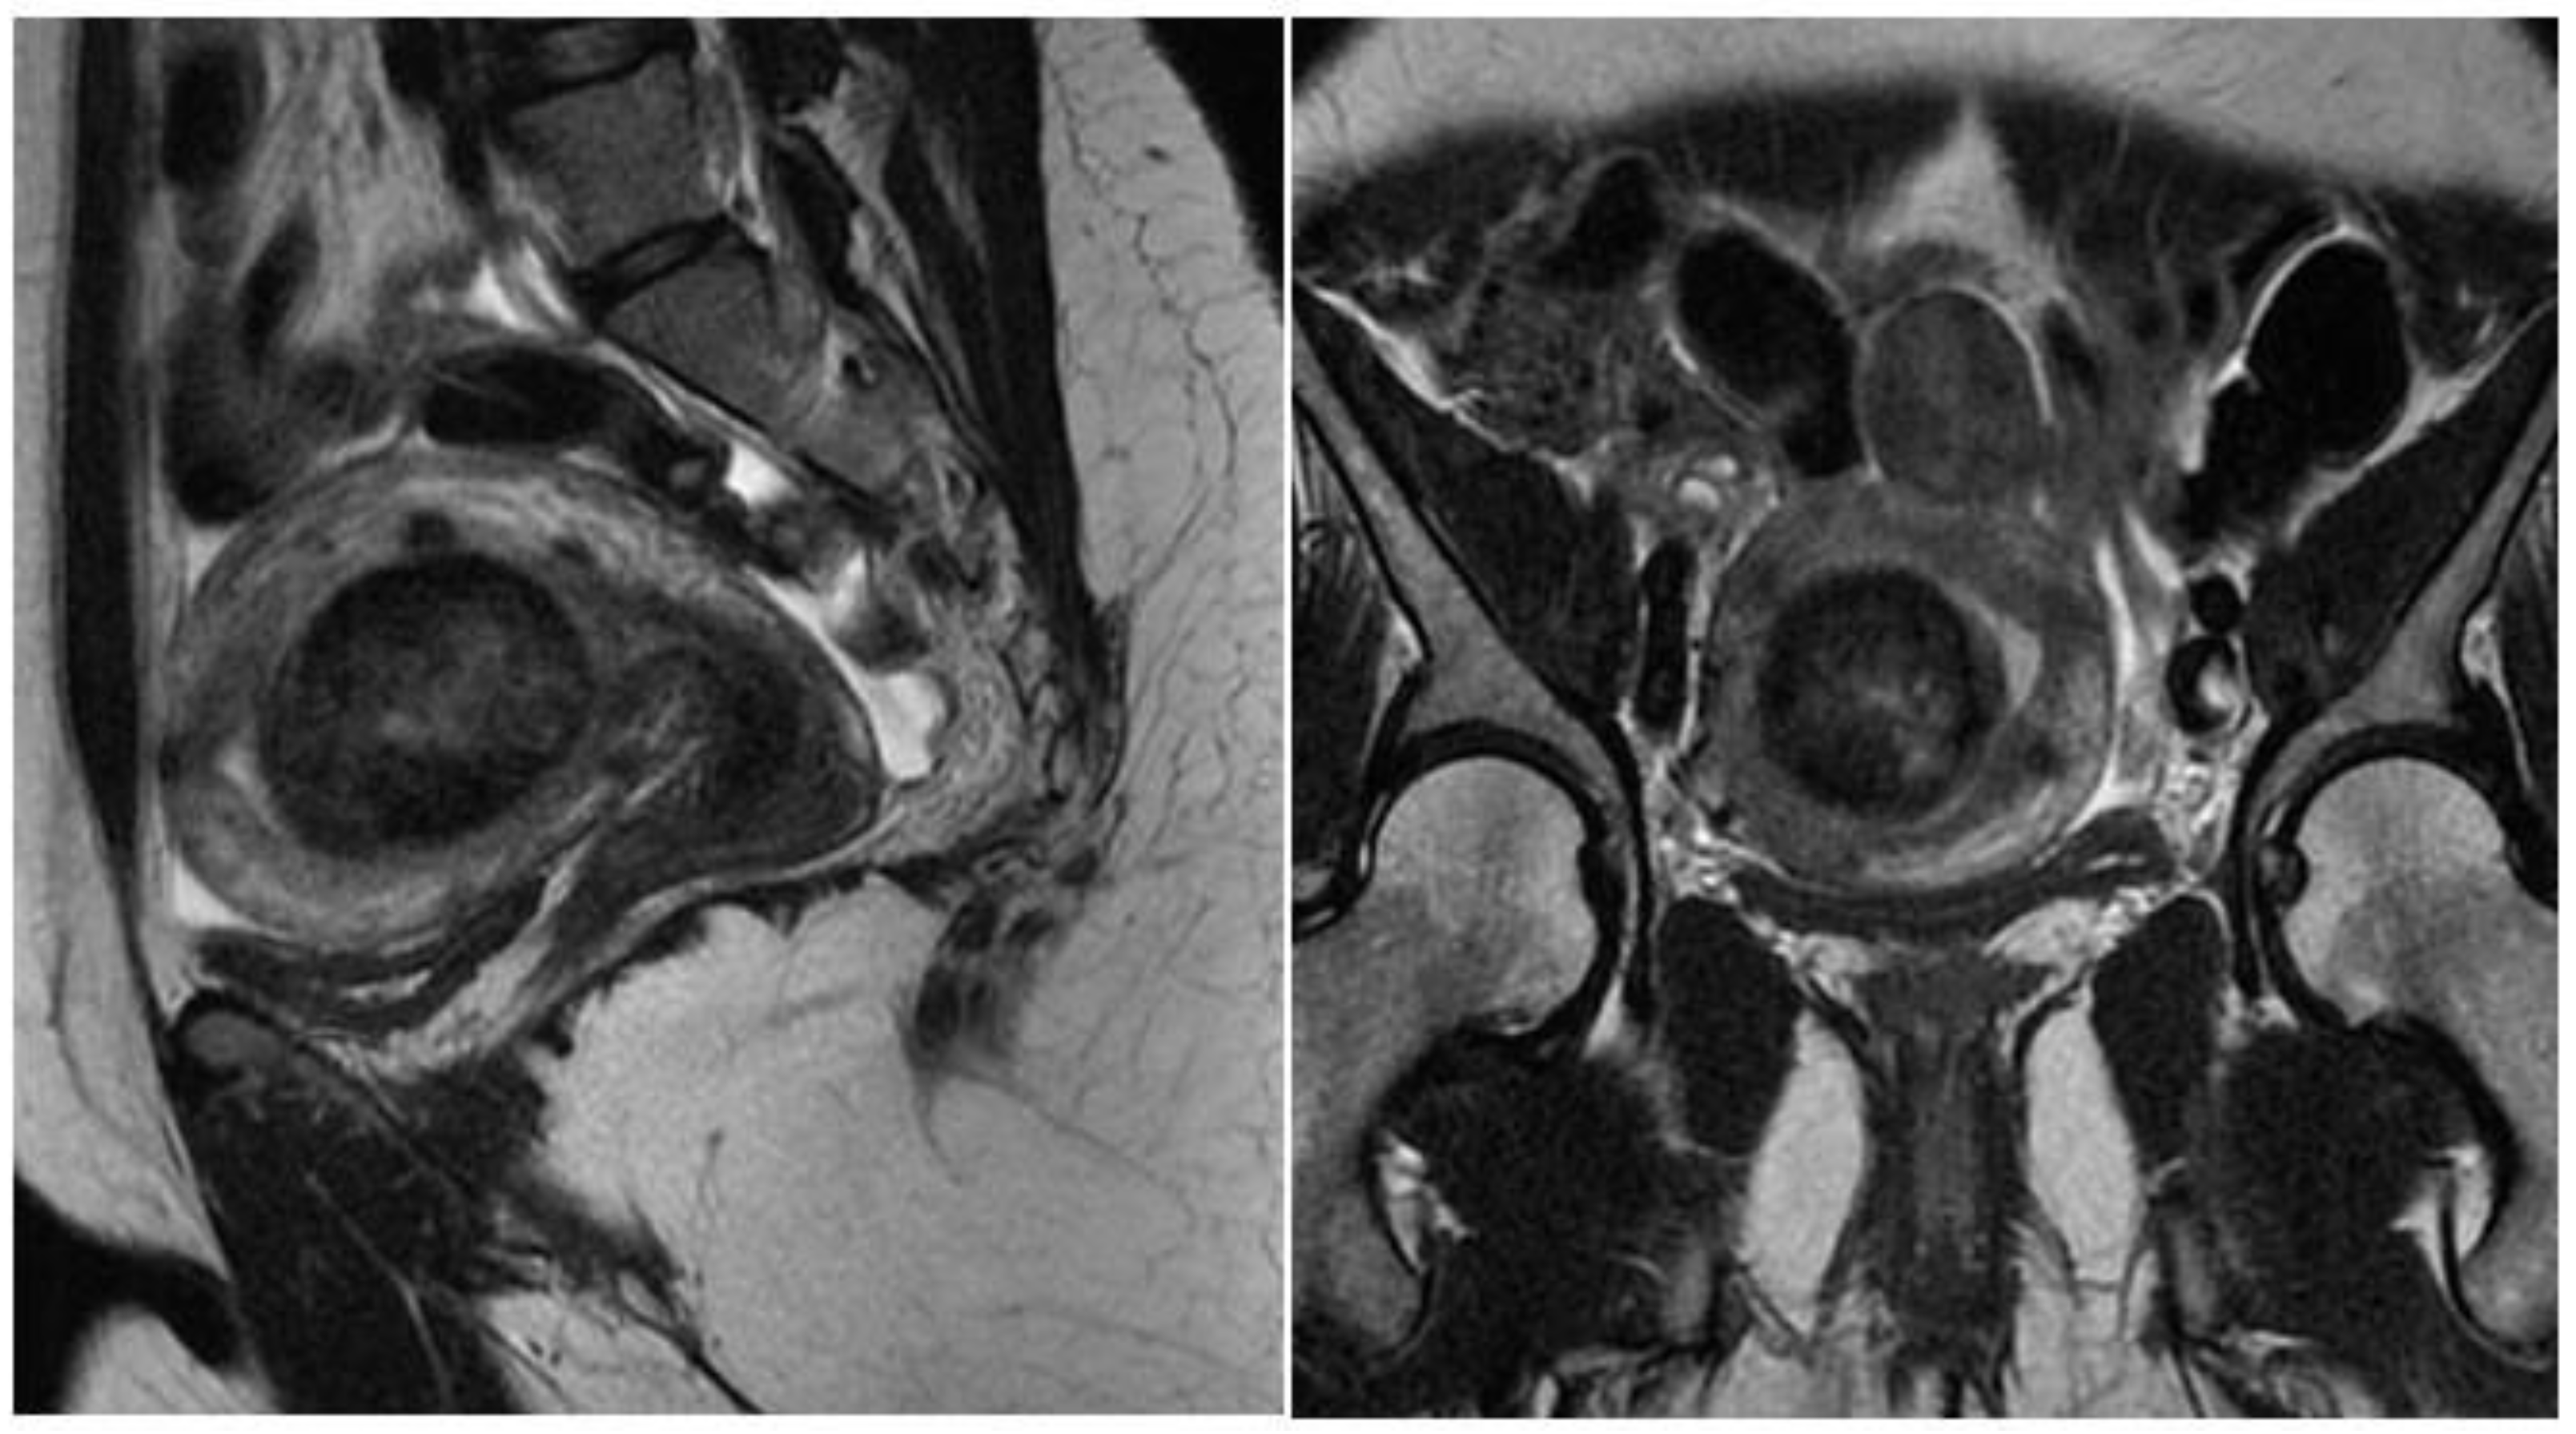

Magnetic resonance imaging of the pelvis (MRI) is indicated in uteri with a volume greater than 375 cm3 or with more than four fibroids [20]. With excellent definition regarding the number, location, size of nodules, and proximity to other myomas, it is used to diagnose adenomyosis and adenomyoma, rule out non-fibroids and sarcomas, and to measure the myometrial mantle. The myometrial mantle refers to the distance between the deepest portion of the myoma in the myometrium and the serosa, being of unique importance in hysteroscopic myomectomy, since confirmation of transmural myoma (the one that reaches the serosa) contraindicates the hysteroscopic approach due to the high probability of uterine perforation during the procedure (Figure 4).

Figure 4. MRI with submucous myoma.